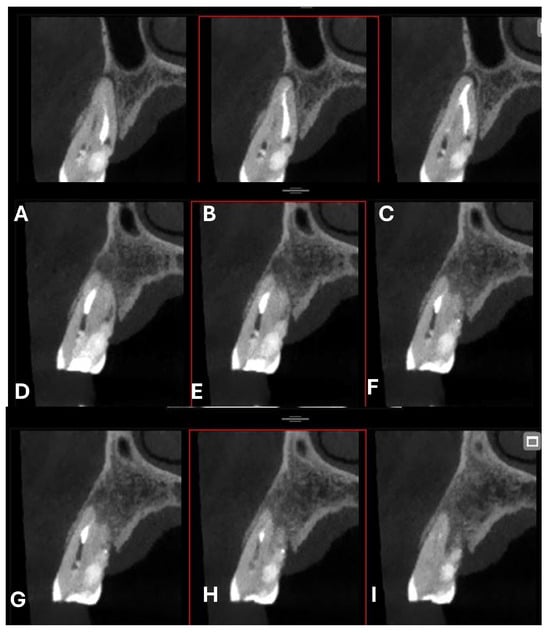

Cross-section CBCT images of tooth 1.4 after six months of healing. (A–I) Sequential scrolling of EPL healing.

Figure 12.

Pano-rex and cross-sectional CBCT images of tooth 1.4 after six months of healing. (A,B) Sequential scrolling of tooth 1.4 after six months of healing. The colored lines crossing the images represent the orthogonal planes (axial, coronal, and sagittal) in the multiplanar reconstruction. Their correct use and orientation allow for an accurate identification of the extent of the lesions in all spatial planes and a detailed analysis of the endodontic anatomy. The green and red letters are the coordinates of the image: A: anterior, R: right, B: bottom, T: Top.

An intermediate follow-up CBCT scan at 6 months was performed to accurately assess the response to treatment in light of both the extent of the lesion and the patient’s systemic comorbidities (Figure 10, Figure 11, Figure 12, Figure 13 and Figure 14).

Figure 10.